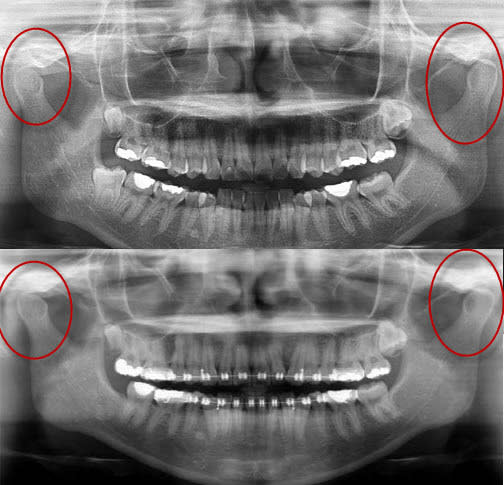

Tu constateras que le nivellement orthodontique de Seespan a entraîné une distoversion molaires inférieure.

Cette distoversion molaire a créé cette fameuse classe II dentaire (et non pas squelettique comme le prétend Seespan) et est de facto à l'origine de l'apparition de la béance à cause des prématurités, comme c'est classique.

Seespan prétend qu'il suffira de corriger ces prématurité pour qu'overjet, open bite et tout le reste disparaisse "sans extraction et sans chirurgie", là il se fiche dedans dans les grandes largeurs, son traitement ne sera pas si simple que ça !

Calme-toi Seepan, le probleme vient peut-etre du fait que tu traites une typologie ethnique totalement differente du type caucasien, les valeurs n'ont aucune valeur de ce cas de figure. Daniel, tout comme moi, pense que le cas est une classe II dificil à corriger, surtout dans le contexte presenté auparavant. La mecanique doit etre bien etudiée, bien dosée et bien appliquée car toute egression de la molaire sous l'effet des elastiques de classe II va contrcarrer le gain dans le sens antero-posterieur. La béance est deja en place, l'ouverture de l'axe facial est deja là et sa re-fermeture n'est pas dit, par la simple suppression des points de prematurité. La classe molaire s'est aggravée, le profil esthetique est moins favorable qu'avant,etc......